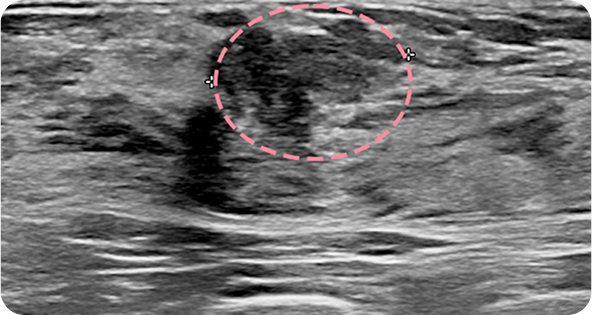

맘모톰시술 후 병리조직검사 결과 상피내암(조기 유방암)

초기로

진단되어 항암치료 없이 간단한 수술로 치료가

가능했습니다. 눈에

잘 띄지 않는 작은 병변까지 확인할 수 있었던 건,

맘모톰의 정밀한

조직검사 기능과 전문의의 정확한 판독이 있었기 때문입니다.